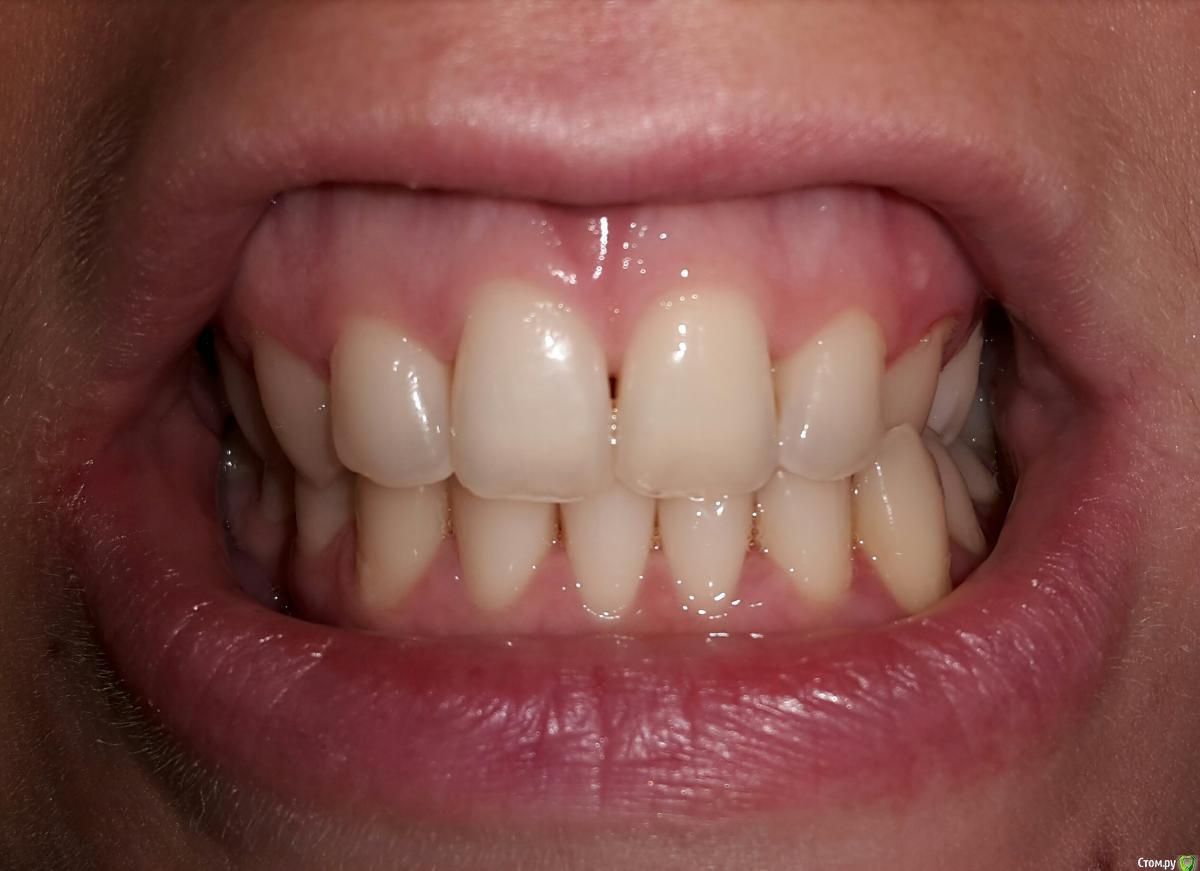

Анастасия Лазарева Опубликовано 15 сентября, 2016 Поделиться Опубликовано 15 сентября, 2016 (изменено) Добрый день, очень прошу совета по своей проблеме. Мне 28 лет. В мае этого года после 2-х часового лечения зубов очень сильно заболела челюсть слева около уха. Чувствую боль также при глотании, иногда отдает в ухо. Больно жевать, особенно жесткую пищу, рот до конца не открывается,максимум на 3-3.5 см. Дальше будто блок. До этого момента в течение многих лет челюсть слева щелкала при зевании и сильном открытии рта, но боли не было, и меня это не беспокоило.Считаю важным отметить, что долгое время я жую все время на правой стороне, тк 6 слева отсутствует с 2005 года. С болью в челюсти обратилась к врачам. Диагноз:двусторонняя болевая мышечно суставная дисфункция внчс..Также отметили неправильный прикус, смещение челюсти, тонус мышц.Предложен план лечения:1. капа. Должна устранить боль в челюсти2. Брекеты для исправления прикуса 3. Имплантация 6 слева.От таких рекомендаций голова кругом... Хотела бы спросить у опытных специалистов прокомментировать мои снимки и фото. Может Вы видите какие-то другие особенности и варианты решения проблемы,которая появилась так внезапно. Заранее очень благодарна за любые рекомендации. Изменено 15 сентября, 2016 пользователем Анастасия Лазарева Ссылка на комментарий